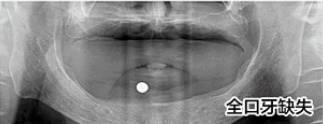

劉先生(花甲之年)全口牙缺失

步入花甲之年的劉先生其實(shí)在40多歲的時(shí)候牙齒就開始松動(dòng),起初想著還可以湊合吃飯,就沒(méi)有怎么管,可是如今年紀(jì)大了,牙齒一顆接著一顆的掉,只能喝粥。

△檢查CT片

劉先生的女兒看見(jiàn)父親在該享福的時(shí)候卻連頓好飯都吃不了,看在眼里,疼在心里,看到活動(dòng)就為父親報(bào)名了。

經(jīng)過(guò)2個(gè)多小時(shí)的種植過(guò)程,劉先生缺牙問(wèn)題解決了,當(dāng)天種好恢復(fù)咀嚼力?,F(xiàn)場(chǎng)露出一口整齊潔白的牙齒,笑著說(shuō):“有個(gè)孝順的女兒真是很大的福氣,現(xiàn)在終于可以好好的吃一頓飯了。”